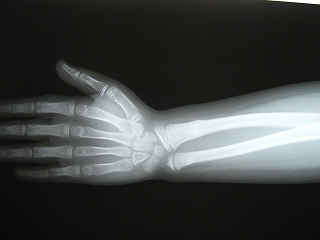

‰E‘O˜rœœÜ

@@”N—î@@8Î@—«

@@•‰“ú@•½¬14”N7ŒŽ27“ú

œÜÇ—á